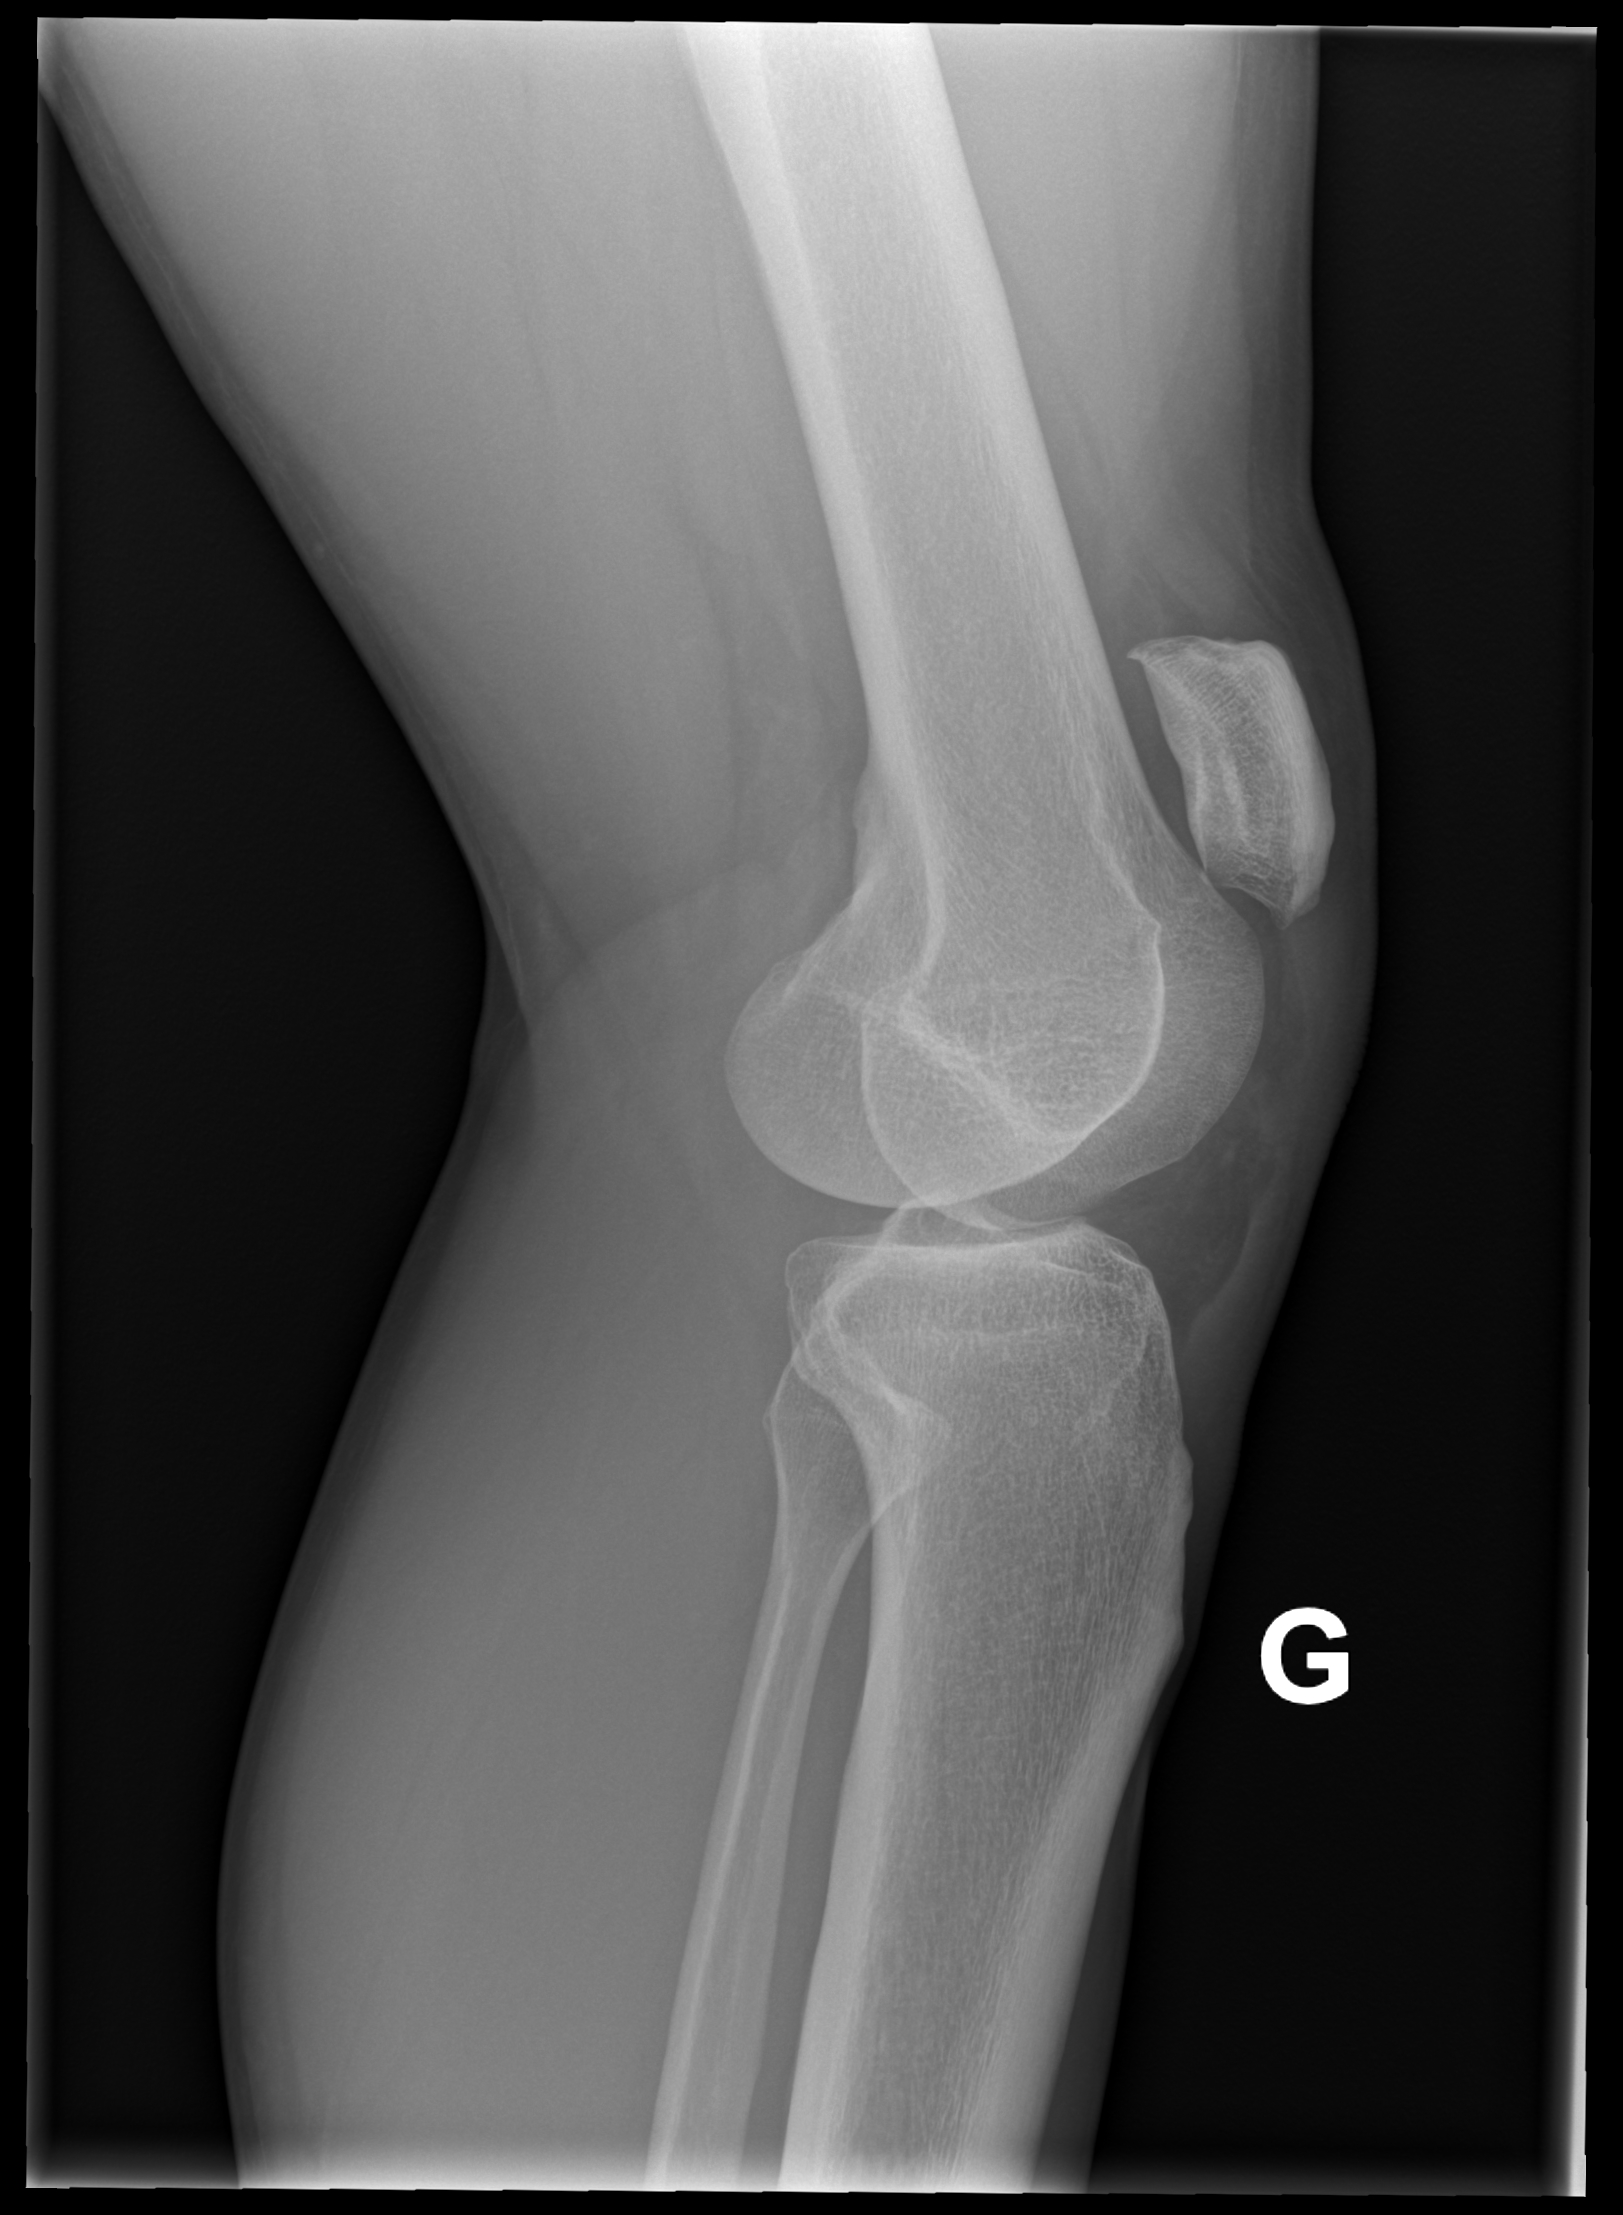

A l’examen clinique, le genou est légèrement tuméfié. La rotule semble ascensionnée et un creux est palpé sur le trajet du tendon rotulien. L’extension active est impossible. Sur les radiographies standards face et profil du genou, la rotule est ascensionnée.

Lorsque l’incidence axiale (ou défilé fémoro-patellaire, genou fléchi à 30°) est réalisée, l’image est décrite comme un « lever de soleil » avec une disparition de l’interligne articulaire et la superposition de la rotule avec les condyles fémoraux.

L’ultrason ou l’IRM peut confirmer le diagnostic de lésion du tendon rotulien et de différencier une rupture partielle d’une rupture complète. Le traitement est chirurgical.